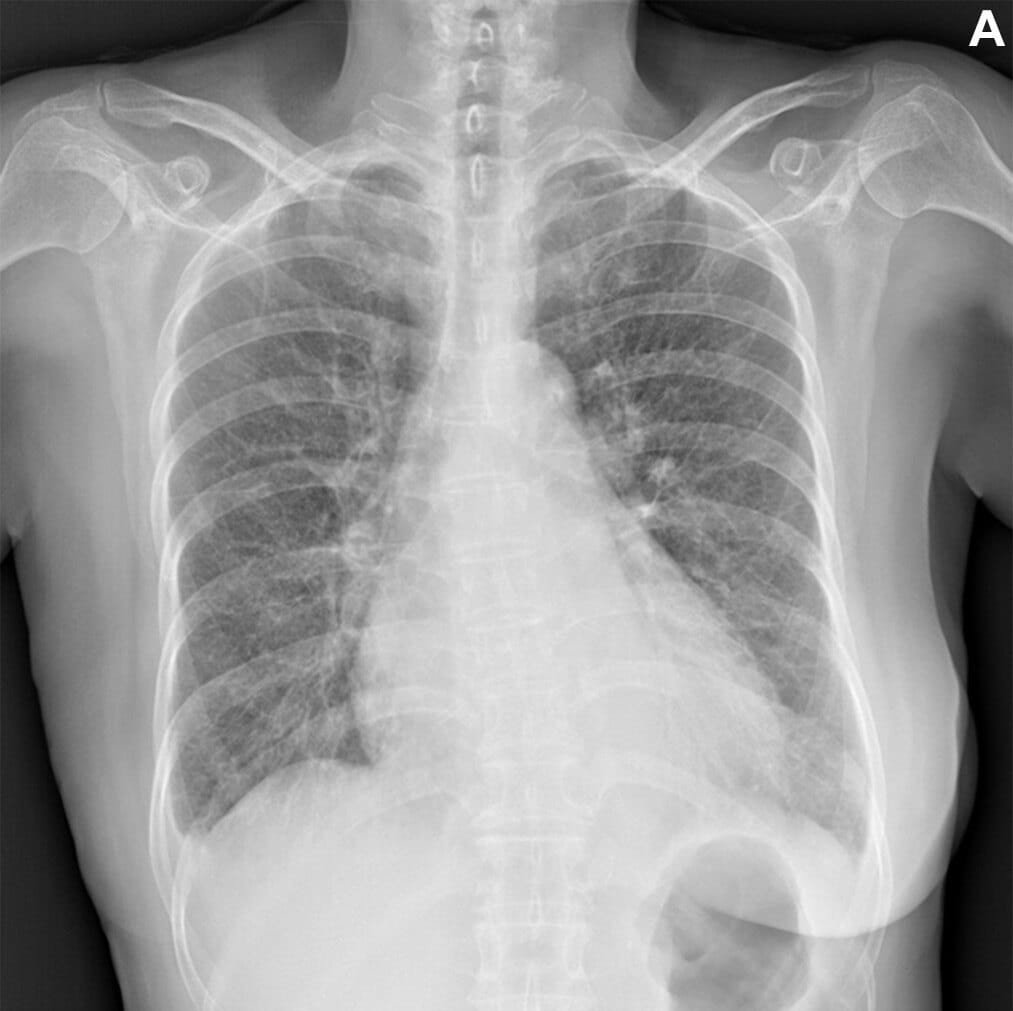

Instance of an acceptable AI– generated breast x-ray report. (A) Anteroposterior chest x-ray in a 68 -year-old female individual that visited the emergency division due to acute-onset dyspnea shows an enlarged heart, reciprocal pleural effusion, and reciprocal interstitial thickening, suggesting cardiac arrest and interstitial pulmonary edema. (B) The AI-generated record properly describes the findings of the x-ray and recommends a feasible medical diagnosis. All 7 thoracic radiologists assessed the AI-generated report as acceptable without revision. RSNA